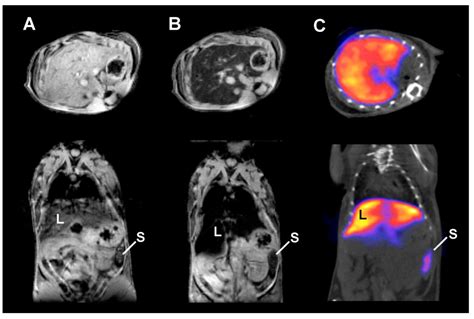

For example, in a CT scan, an iodine-based contrast agent makes blood vessels and organs appear brighter (whiter) on the resulting image, effectively "lighting up" the area of interest. In MRI, different types of agents, such as gadolinium, affect the relaxation times of hydrogen protons, which in turn alters the signal intensity of tissues, helping to highlight abnormalities like tumors or areas of inflammation that might otherwise blend into the background.

• Gadolinium-based agents: Commonly used in MRI. These substances alter the magnetic properties of surrounding water molecules in the body, providing high-resolution images of soft tissues.